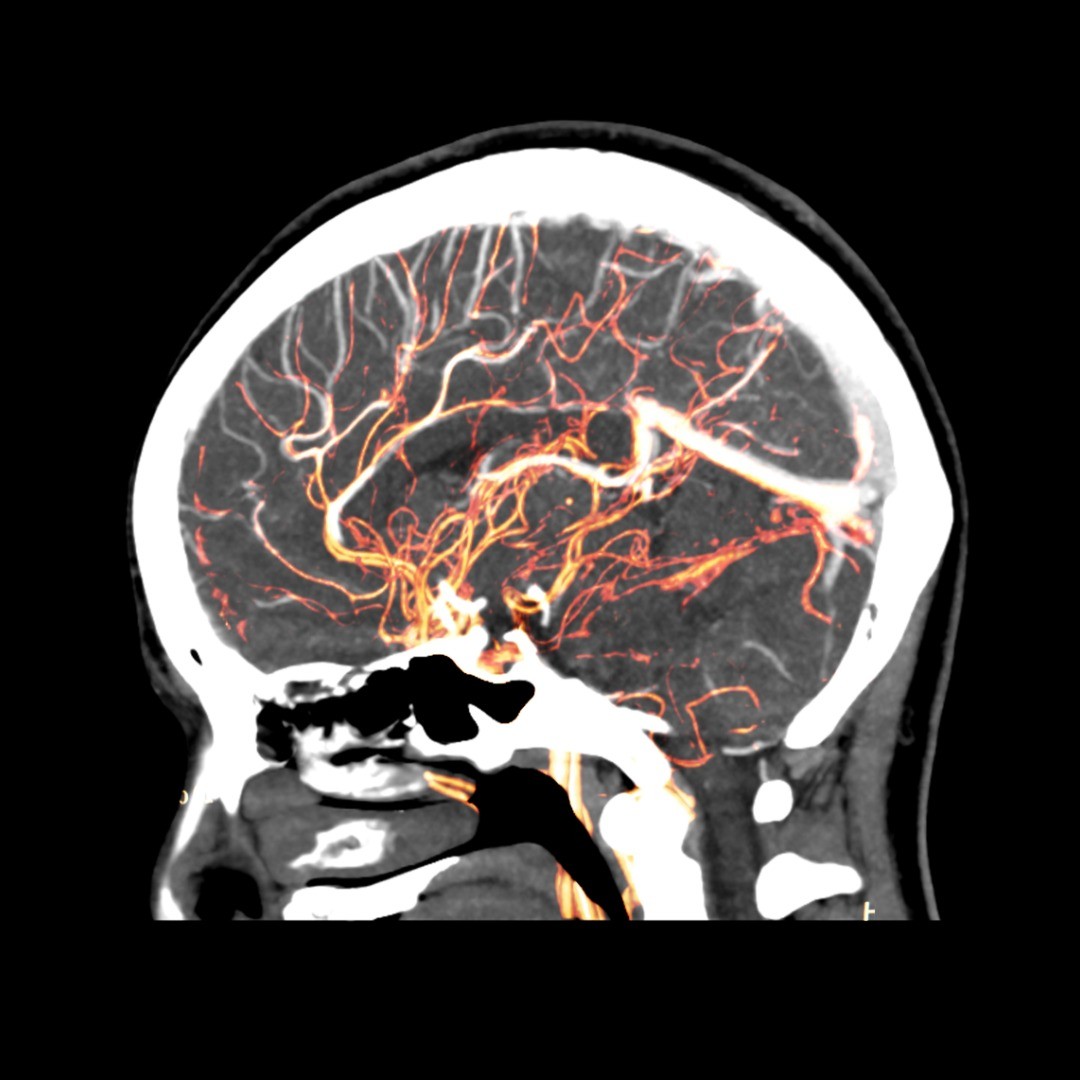

Cerebral aneurysm treatments depend on a variety of factors: whether the aneurysm, a bulge in the wall of the artery, is pre-rupture or after an event, your health and age, how small or large the aneurysm is, and whether it is causing neurological symptoms among other risk factors.

Surgical Clipping – During this surgical procedure, a tiny clip is attached to the base of the aneurysm to prevent blood flow— thereby decreasing the likelihood of it bursting or rupturing if it’s pre-rupture or to treat a ruptured aneurysm. To reach the aneurysm, the neurosurgeon performs a small craniotomy, which temporarily removes a portion of the skull, and an incision in the brain covering called the dura mater allows the surgeon to carefully retract the brain and trace the affected artery to the aneurysm. Once there, the clip is placed on the neck of the aneurysm.